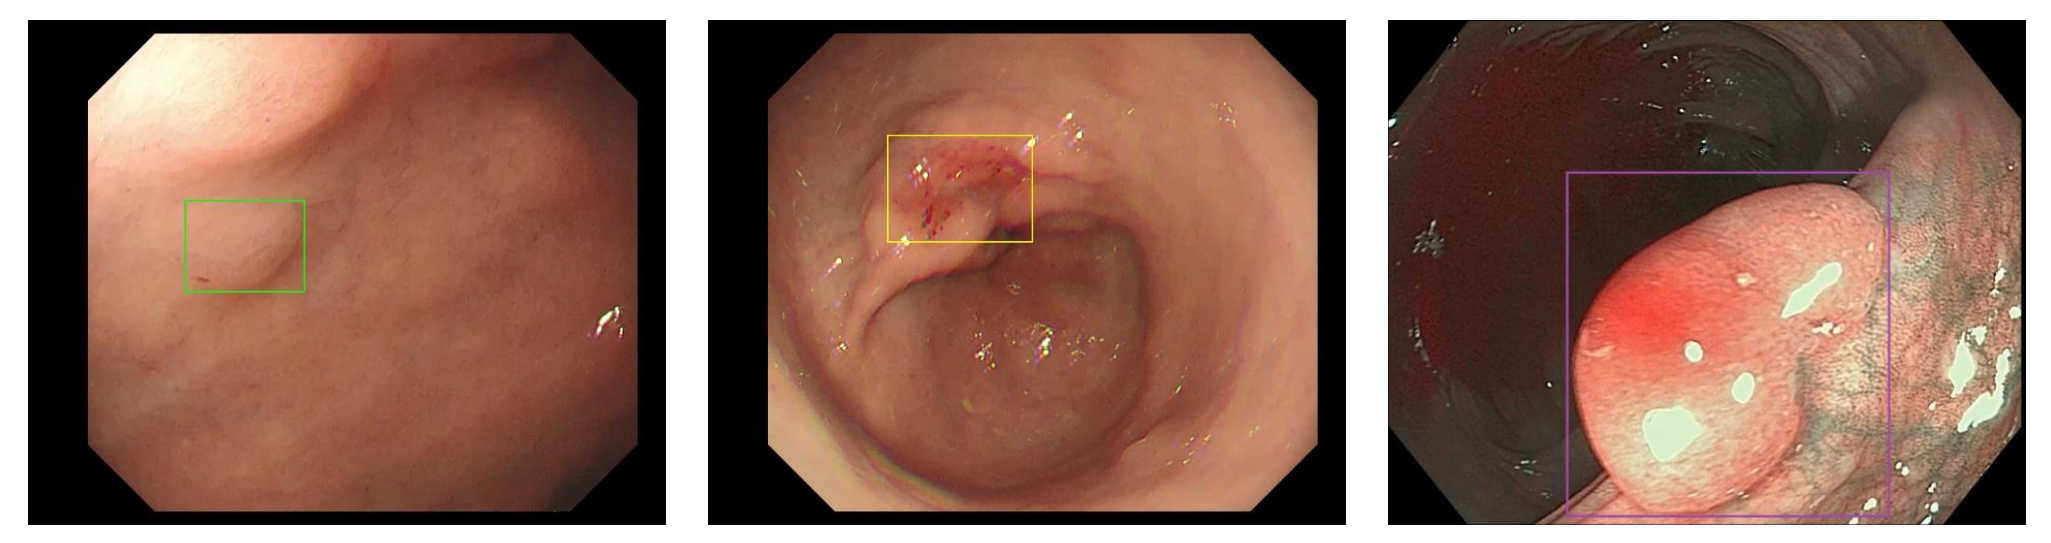

Aohua Endo Mate – công nghệ trí tuệ nhân tạo tiên tiến hỗ trợ quy trình nội soi, nâng cao chất lượng chẩn đoán và điều trị.

- Tự động phát hiện tổn thương theo thời gian thực và đánh giá mức độ tổn thương bằng các màu sắc khác nhau.

- Kiểm soát chất lượng nội soi

| Nội soi đường tiêu hóa trên:

| Nội soi đường tiêu hóa dưới: